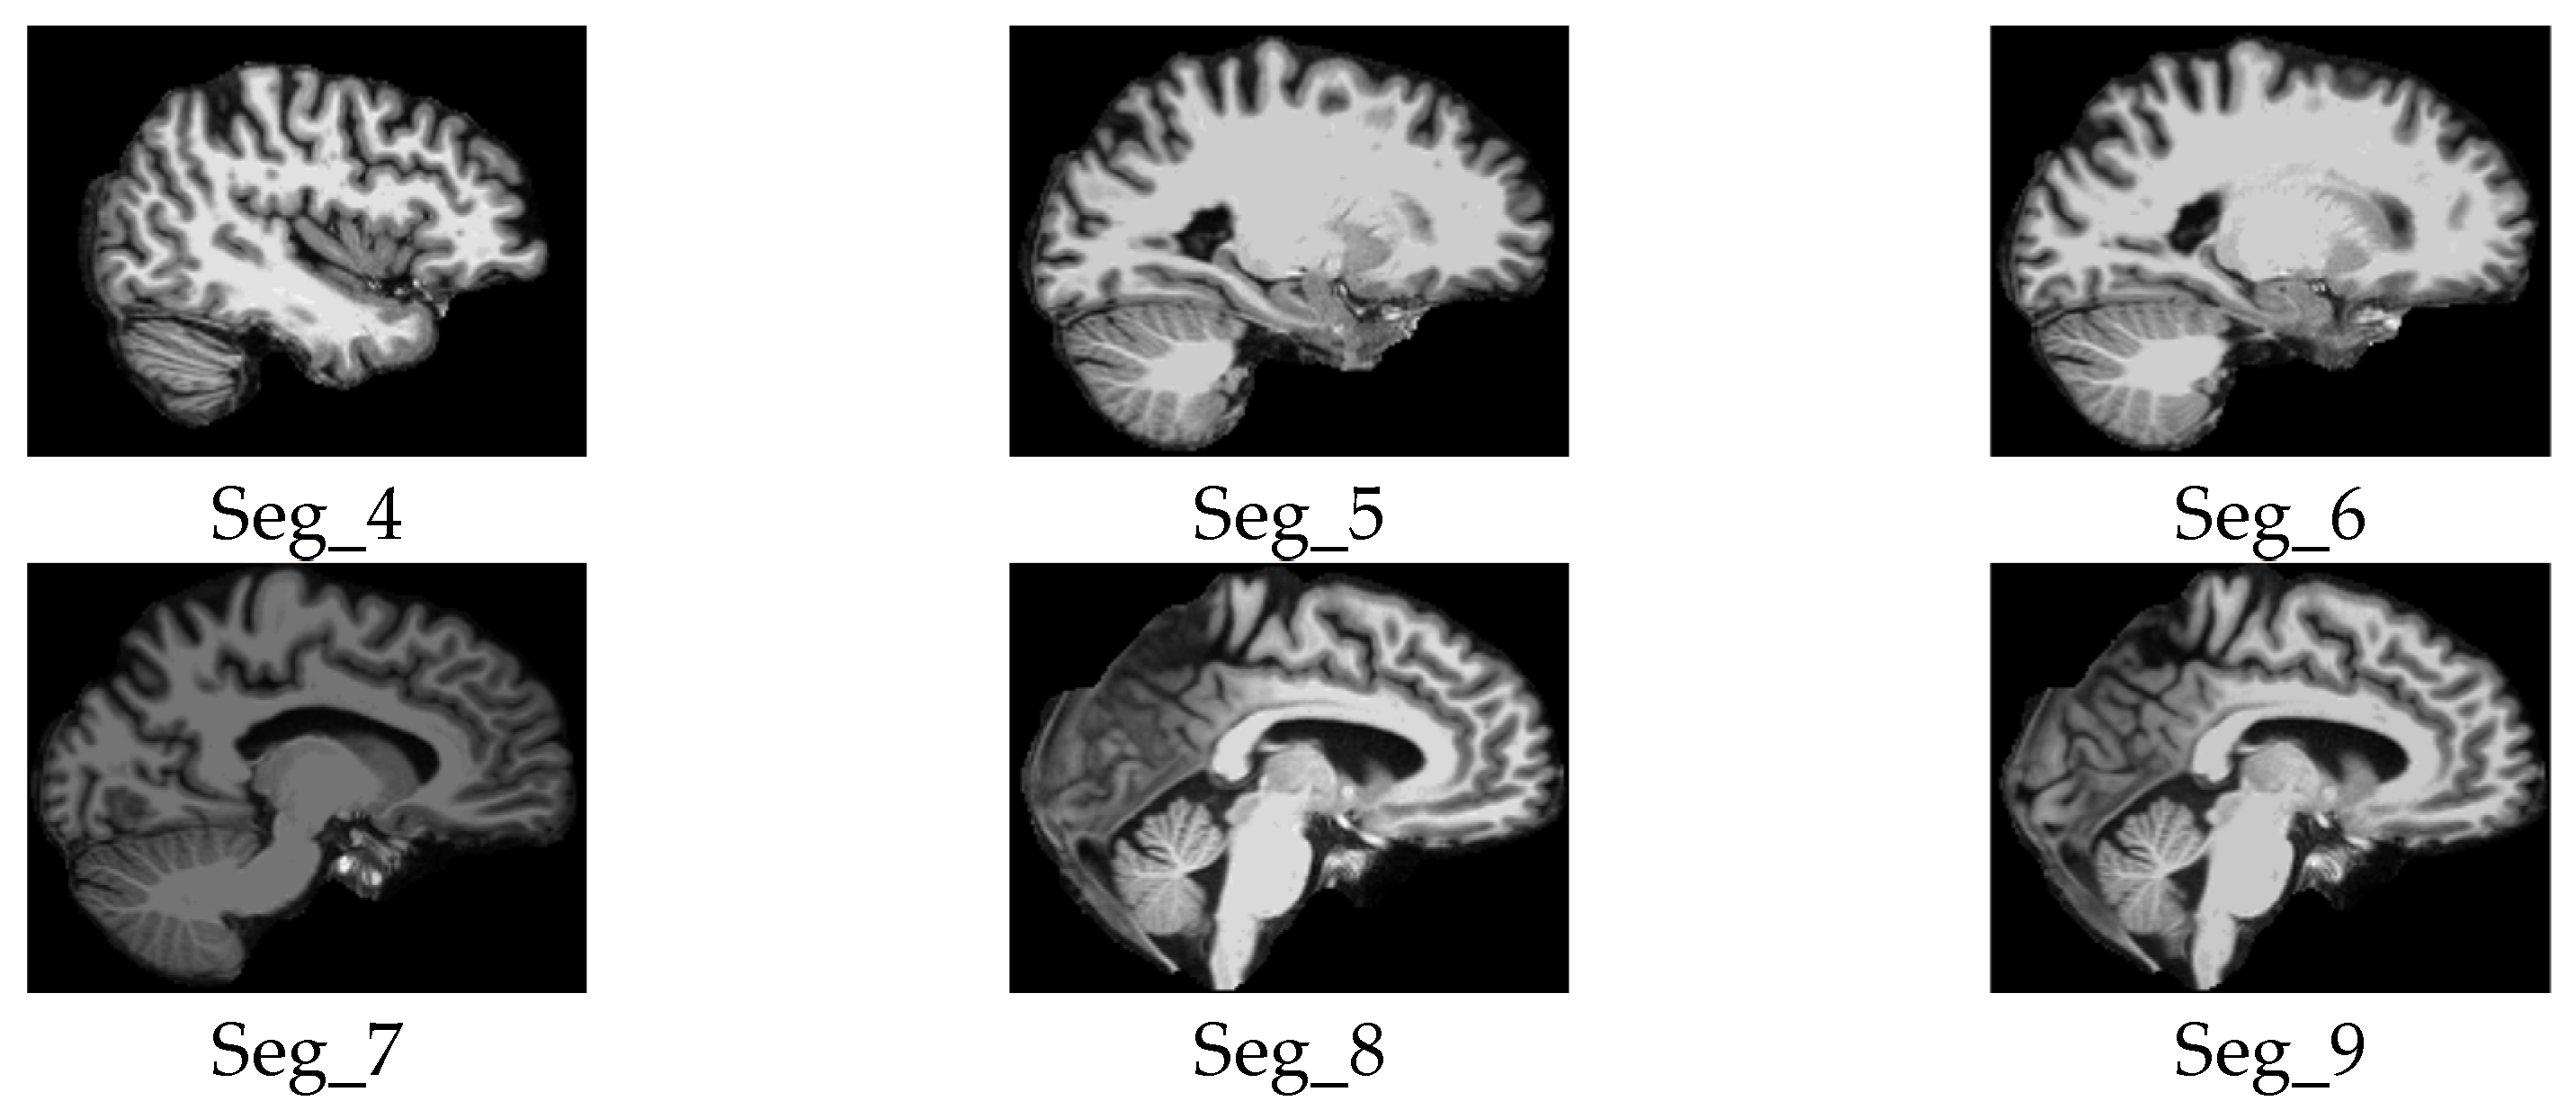

3.3. Automated 2D Slice Selection